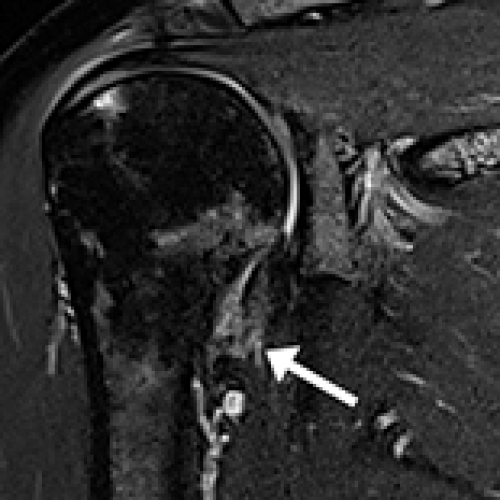

Shoulder Injury Related to Vaccine Administration (SIRVA) in 16 Patients Following COVID-19 Vaccination Who Presented to Chiropractic, Orthopedic, and Physiotherapy Clinics in Hong Kong During 2021

11 Jul 2022 : Clinical Research

Eric Chun-Pu Chu